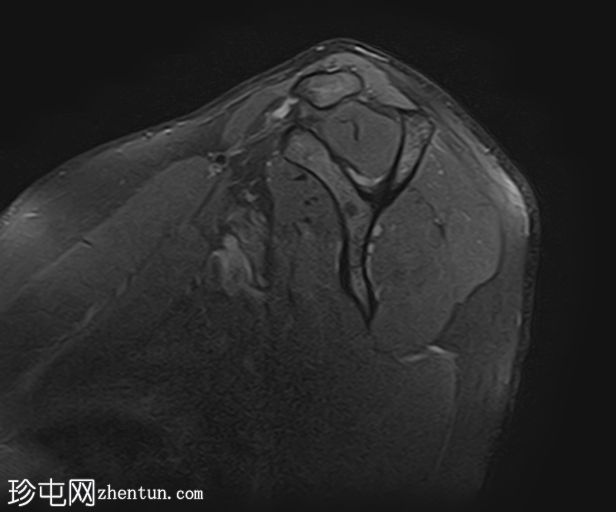

MRI

4.jpg

冠状位T2加权像

脂肪抑制像

冈上肌腱上部纤维可见约25 x 1.2 mm的低信号肌腱内病变,符合钙化性肌腱炎的影像学表现

冈上肌腱滑囊侧纤维可见液体信号增高,符合肌腱病

II型肩峰(弯曲型)

肩峰下滑囊内可见轻度液体信号,提示轻度滑囊炎